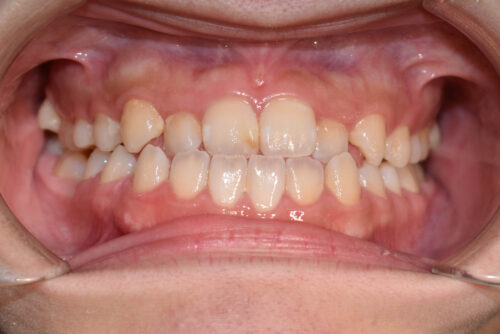

ワイヤー8か月後です。

本症例のように

歯科矯正用アンカースクリュー(デュアル・トップオートスクリュー)を利用し

下顎の後方移動を行うことで

歯を抜かない非抜歯矯正治療でも

受け口を整えることができます。